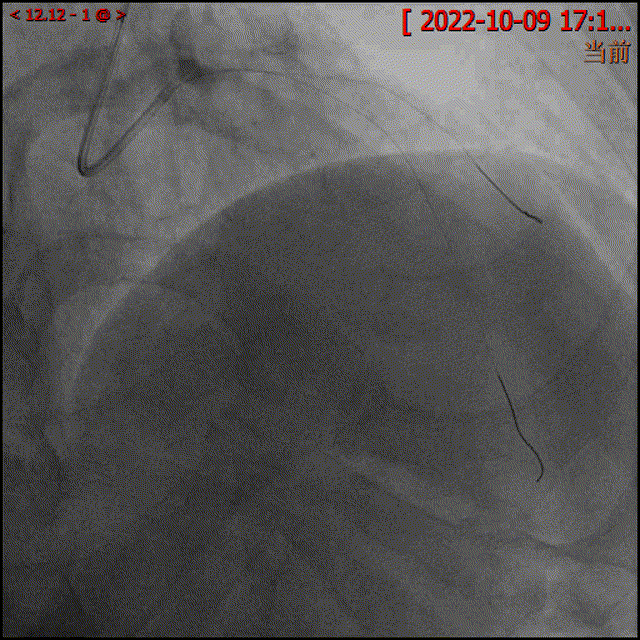

手术过程中,葛均波院士首先分别在LAD及D1各送入一根导丝。随后,为了更为精准地评价冠脉病变性质及严重程度,术者沿LAD导丝将微创阿格斯™OCT成像导管置于LAD中段,回撤成像可以清楚地看到LAD局部斑块负荷重,以纤维脂质斑块为主,管腔局部重度狭窄,病变长度25.4mm,狭窄最重处面积仅1.79mm²。

OCT示LAD中远段管腔重度狭窄,可见纤维脂质斑块